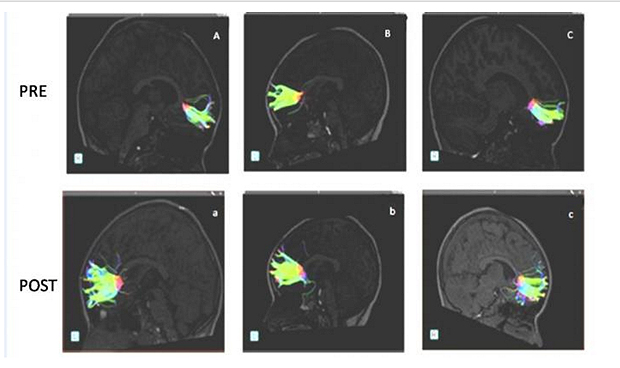

Para llegar a estas conclusiones, los autores del estudio utilizaron una técnica de imagen conocida como tensor de difusión de imagen (DTI) del cerebro, un subtipo de resonancia magnética que calibra el grado de vibración captada en el espacio que rodea a las neuronas.

Los resultados de la DTI en este trabajo han revelado un claro aumento de ese parámetro que mide la vibración extracelular además de la presencia de fibras nerviosas más alargadas en diferentes áreas del cerebro pero, muy en especial, en una que los neurólogos y anatomistas conocen como el fascículo accesorio.

Pero lo esencial reside en que el entrenamiento muscular tendió a armonizar esa vibración del espacio que rodea a las células nerviosas acercando el perfil del cerebro del niño con TDAH al que se observa en el menor normal.